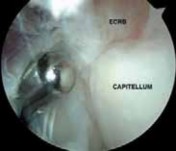

With the proximal medial portal as the standard viewing portal, the 30-degree scope is advanced just past the radial head to visualize the lateral joint capsule and undersurface of the ECRB origin ( TECH FIG 2A).

The capsule often adheres to the undersurface of the ECRB and can have varying degrees of degeneration, presenting as linear tears (type II lesion), fraying, or yellowish fatty infiltration, or it can have a thin, translucent appearance ( TECH FIG 2B).

- ### TECH FIG 2 • A. Type I lesion showing synovitis and fraying of the lateral joint capsule. B. Type II lesion showing linear tear of the joint capsule and the extensor carpi radialis brevis (ECRB) tendon near its insertion site.

- C. Type III lesion showing complete avulsion and retraction of the lateral capsule and ECRB tendon. D. Fatty degeneration of the ECRB tendon ( arrow ), which is overlying the ECRL muscle–tendon. E. A 4.5-mm shaver is used for the initial débridement of the ECRB, which is in close proximity to the capitellum ( C ) and radial head ( R ). F. Débridement of the pathologic ECRB tendon and capsule with healthy-appearing extensor carpi radialis longus superficial. G. A 4.0-mm abrader is the final step to decorticate the